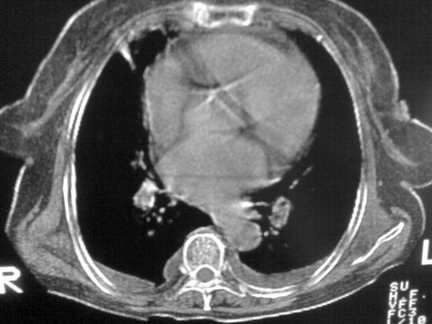

标题: CT13142:女 80 胸闷、气短、1w [打印本页]

标题: CT13142:女 80 胸闷、气短、1w

双侧胸腔积液

缩窄性心包炎

左室为主的心脏增大。

右肺感染;双侧胸腔少量积液,心影增大,可能与心功不全有关;胸内甲状腺肿。

右肺炎性变,双侧甲状腺肿,胸膜肥厚,心影增大考虑心功能不全.

胸内甲状腺肿;右肺中叶感染;双侧胸腔少量积液;心影增大,考虑有心功能不全。